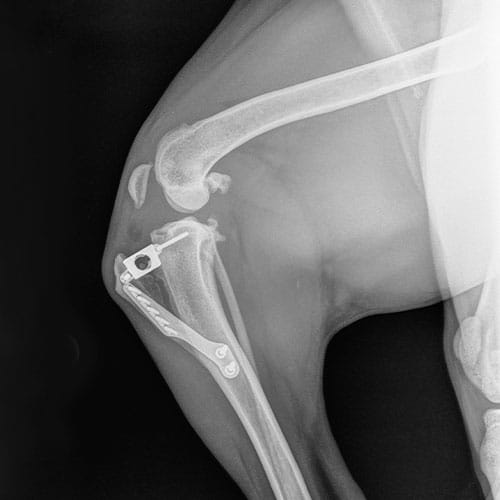

• Diagnosis: Our veterinarians use a combination of physical examinations, palpation tests like the cranial drawer test, and often radiographs to confirm CCL tears. Early diagnosis can prevent further damage to the joint.

• Surgical Repair: The most effective treatment for CCL tears, especially in active or large dogs, includes various techniques like extracapsular stabilization, TPLO (Tibial Plateau Leveling Osteotomy), or TTA (Tibial Tuberosity Advancement). These surgeries aim to stabilize the knee joint and reduce arthritis progression. Generally speaking, TPLO is superior to TTA, which is superior to extracapsular technique but our doctors will help you decide what is optimal for you and your pet.